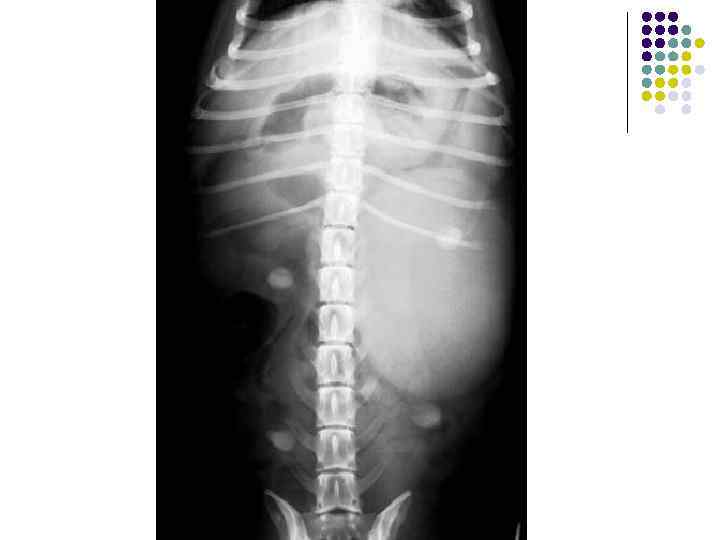

Камни мочевого пузыря